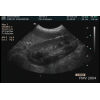

Rein gauche

Durée. 3:37                 Dr Guy Beauregard